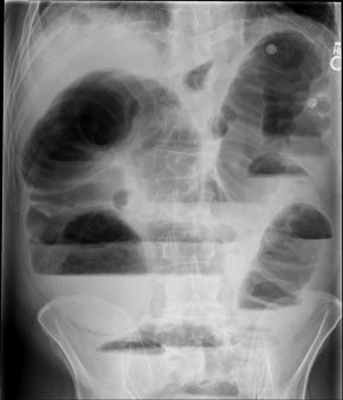

Рентгенологическое исследование является основным специальным методом диагностики ОКН. При этом выявляются следующие признаки:

- Чаша Клойбера – горизонтальный уровень жидкости с куполообразным просветлением над ним, что имеет вид перевернутой вверх дном чаши. При странгуляционной непроходимости могут проявляться уже через 1 час, а при обтурационной непроходимости — через 3-5 часов с момента заболевания. Количество чаш бывает различным, иногда они могут наслаиваться одна на другую в виде ступенчатой лестницы.

- Кишечные аркады. Получаются, когда тонкая кишка оказывается раздутой газами, при этом в нижних коленах аркад видны горизонтальные уровни жидкости.

- Симптом перистости (поперечная исчерченность в форме растянутой пружины) встречается при высокой кишечной непроходимости и связан с растяжением тощей кишки, имеющей высокие циркулярные складки слизистой. Контрастное исследование желудочно-кишечного тракта применяется при затруднениях в диагностике кишечной непроходимости. Больному дают выпить 50 мл бариевой взвеси и проводят динамическое исследование пассажа бария. Задержка его до 4-6 часов и более дает основание заподозрить нарушение двигательной функции кишечника.

Рентгенологическая диагностика острой кишечной непроходимости. Уже через 6 ч от начала заболевания имеются рентгенологические признаки кишечной непроходимости.